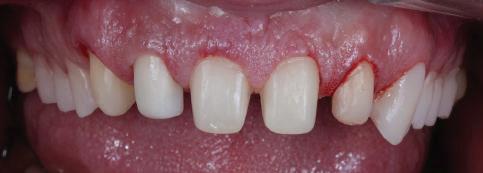

11Dental Tribune Bulgarian Edition / октомври 2022 г. Преди лечението Фиг. 1 Фиг. 2 Фиг. 3 Фиг. 4 Фиг. 5 Фиг. 6 Фиг. 7 Фиг. 9 Фиг. 10 Фиг. 11 Фиг. 8 Фиг. 12 Фиг. 13

13Dental Tribune Bulgarian Edition / октомври 2022 г. След лечението За авторите: Д-р Калин Маринов е специалист в областта на имплантологията, протетиката и естетичната хирургия. Завършил е дентална медици на в София през 2012 г. През 2014 г. основава Sky Dental Clinic. Бил е на обмен ни начала в катедра „Протетика“ на Университета по дентална медицина във Фрайбург, Германия. Живял е и е практикувал в Мелбърн, Австралия, и е посеща вал курсове и лекции в Италия, Швейцария, Германия с насоченост в естетич ната хирургия и имплантология, както и тоталната рехабилитация на устна та кухина чрез импланти. Зт. Стефан Петров основава собствена лаборатория през 2006 г. Официален демонстратор на GC за България, като от 2015 г. е KOL за Източна Европа. Инструктор е на Straumann за България. Лаборатория та му има сертификат за пилотна лаборатория на Micerium – Италия. Носител е на множество награди в денталния конкурс „Усмивка на годината”. Носител е на награда CERAMISTS MASTER CUP с д-р Софиен Риахи в престижния международен конгрес CERAMISTS – NO LIMITS 2015 г. Изнася лекции и провежда курсове в редица европейски страни. Фиг. 37 Фиг. 40 Фиг. 43 Фиг. 45 Фиг. 47 Фиг. 50 Фиг. 48 Фиг. 49 Фиг. 41 Фиг. 44 Фиг. 46 Фиг. 42 Фиг. 38 Фиг. 39